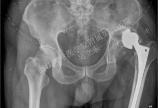

男性,58岁,报社职工因DDH+OA行全髋手术后5年手术侧髋关节术后出现疼痛不适即述不适,活动受限,近1年来加剧,出现夜间疼痛检查:左下肢短缩,髋内收畸形,屈曲活动明显受限ESR:25mm/h,CRP:12术中所见术中发现局部炎性肉芽肿术中快速冰冻切片提示:30-40个中性粒细胞/高倍镜视野考虑假体深部感染手术方法:予彻底清创假体拆除,术中发现髋臼后壁明显缺损抗生素骨水泥Spacer填充术后3月,血沉:8mm/h         C反应蛋白:3手术切口愈合良好予二期全髋关节置换手术术中髋臼处因后壁骨缺损明显,使用Cage+异体骨植骨重建髋臼,股骨使用Solution生物柄重建术后复查片术后5年随访,髋部活动明显改善,跛行不明显